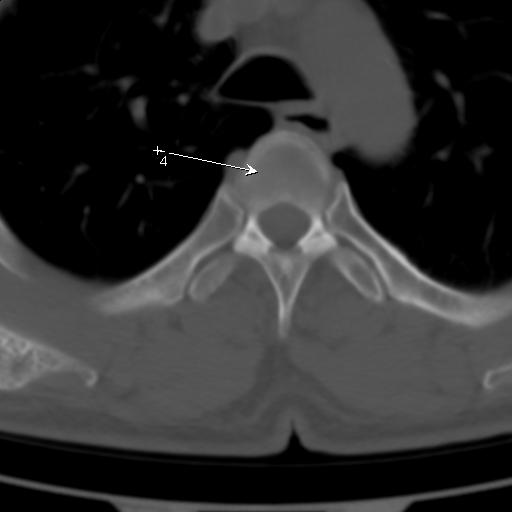

标题: CT25189:胸椎ct,请会诊!

既往食管癌,现行ct检查!

中上段食道癌,椎体轻度退变。

支持中上段食道癌,椎体轻度退变,必要时做ect。